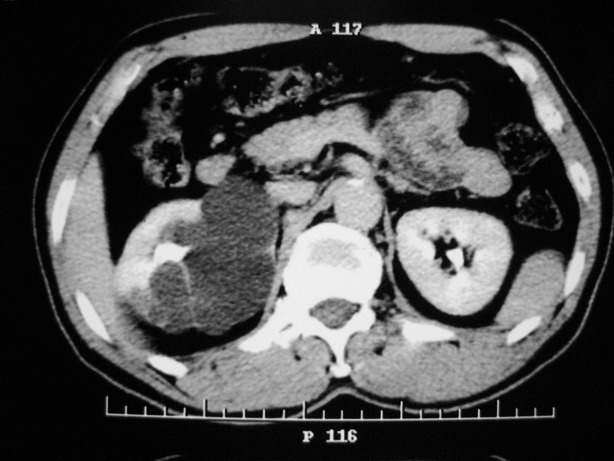

收集期:

延迟期造影剂没有进入囊性病灶内考虑多发性肾囊肿,包括一个盂旁囊肿。

肾盂旁多囊性占位,有实性成分,增强有轻度强化,收集期病变内无造影剂显影。诊断肾盂旁囊肿,有实性成分无法解释,查书后诊断为:多房性囊性肾瘤!!不知大家同意否?????????对本病知道不多,望大家不吝赐教!!

囊间间隔强化与肾实质相仿,还是支持多发囊肿,定期复查